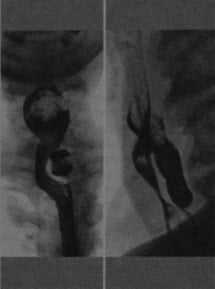

Рентгеноскопия с контрастированием бариевой взвесью: дивертикул Ценкера, сдавливающий пищевод. В левой передней прямой проекции визуализируется дивертикул слева от средней линии. В правой боковой проекции дивертикул выглядит как заполненный барием мешок позади пищевода.

• Дивертикул Ценкера выглядит как заполненное контрастом мешковидное выпячивание задней стенки шейного сегмента пищевода:

о Располагается сразу же над перстневидно-глоточной мышцей на уровне 5-6 шейных позвонков

о Может обнаруживаться выбухание или утолщение перстневидно-глоточной мышцы

о Сужение просвета в области глоточно-пищеводного перехода за счет давления извне

о Крупные дивертикулы могут выбухать латерально (влево) или приводить к сдавливанию шейного сегмента пищевода

(Справа) На рентгенограмме в боковой проекции, полученной во время проглатывания бариевой взвеси, визуализируется мешковидное выпячивание со стороны задней стенки в области глоточно-пищеводного перехода. (Слева) На рентгенограмме, выполненной во время рентгеноскопии глотки и пищевода с бариевой взвесью, визуализируется большой дивертикул в области глоточно-пищеводного перехода, распространяющийся в средостение. Пищевод смещен в сторону, его просвет сужен за счет объемного воздействия дивертикула. Обратите внимание, что контрастное вещество определяется также и в трахее, попав туда в результате аспирации.